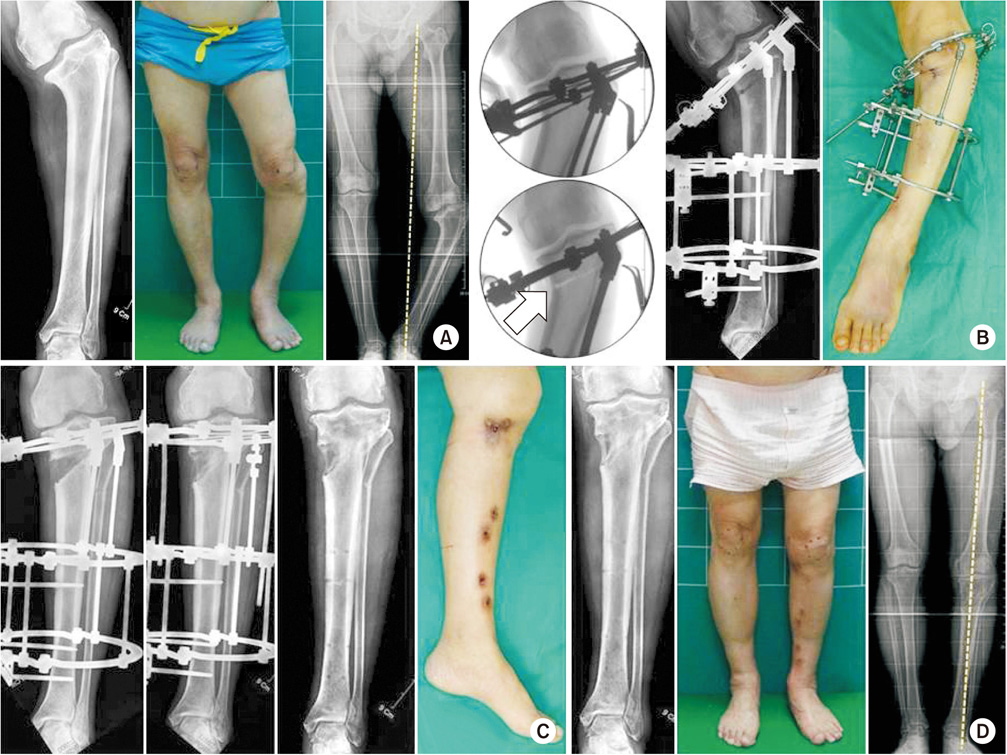

(A) A 67-year-old man, who was suspected to have growth plate injuries in childhood, was confirmed to have varus deformity in the left proximal tibia, and mechanical axis was shifted medially. (B) Because center of rotation of angulation was very close to the joint, fixing the plate was difficult and the correction angle was high; hence, acute correction was expected to be difficult. After attaching the Ilizarov external fixator, osteotomy was performed with the hinge placed outside the convexity (arrow). (C) A progressive distraction was performed to correct the varus deformity, and the external fixator was removed 5 months after sufficient bone maturation. (D) After about 10 months postoperatively, we confirm that the mechanical axis was more improved than before surgery.

Fig. 6 (A) A 67-year-old man, who was suspected to have growth plate injuries in childhood, was confirmed to have varus deformity in the left proximal tibia, and mechanical axis was shifted medially. (B) Because center of rotation of angulation was very close to the joint, fixing the plate was difficult and the correction angle was high; hence, acute correction was expected to be difficult. After attaching the Ilizarov external fixator, osteotomy was performed with the hinge placed outside the convexity (arrow). (C) A progressive distraction was performed to correct the varus deformity, and the external fixator was removed 5 months after sufficient bone maturation. (D) After about 10 months postoperatively, we confirm that the mechanical axis was more improved than before surgery.